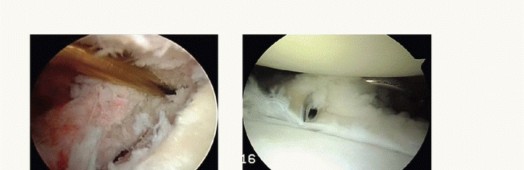

Knot Tying, Capsular Plication, and Construct Finalization

If utilizing knotted anchors, arthroscopic knot tying must be precise to avoid creating prominent knot stacks that can abrade the articular cartilage of the humeral head. We typically utilize a sliding, locking knot (such as a Weston or SMC knot) followed by three alternating half-hitches on alternating posts. The post limb must be the one that exits the anchor directly, ensuring the knot sits securely on the labral tissue, compressing it against the decorticated bone bed.

As each knot is tied, the surgeon must visually confirm the restoration of capsular tension and the recreation of the labral bumper. The axillary pouch should appear visibly reduced in volume, and the humeral head should be centralized within the glenoid fossa.

Image